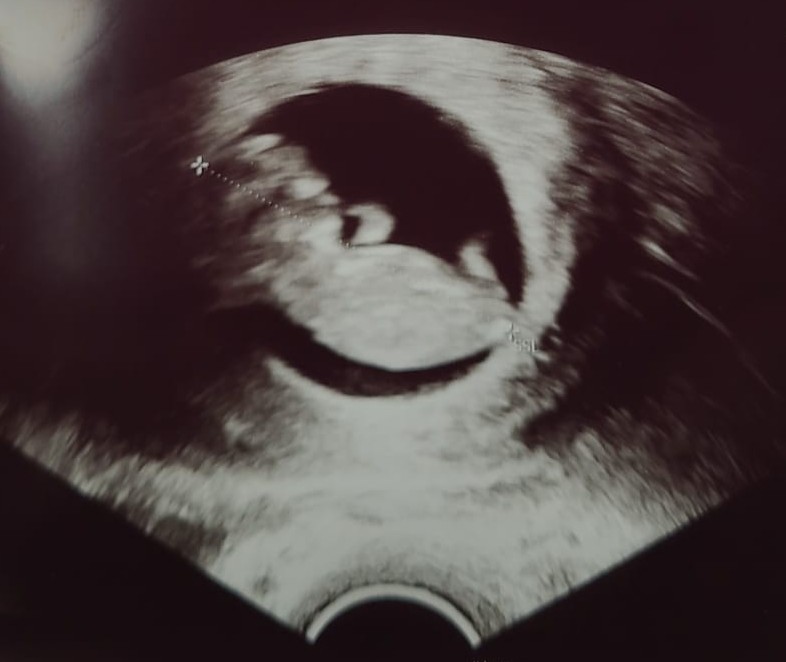

12-week ultrasound scan

The 12-week scan is one of the most anticipated moments in early pregnancy, marking an important milestone in your journey to parenthood. Also known as the dating scan or nuchal translucency scan, this routine ultrasound provides crucial information about your baby's development and helps establish your due date. Understanding what happens during this scan can help you feel more prepared and confident as you approach this exciting appointment.

• Images of your baby appear on the screen, and you will be able to see your baby for the first time

This is the most important measurement for dating your pregnancy. The sonographer measures from the top of your baby's head to their bottom. At 12 weeks, this measurement is typically around 5-6 centimetres.